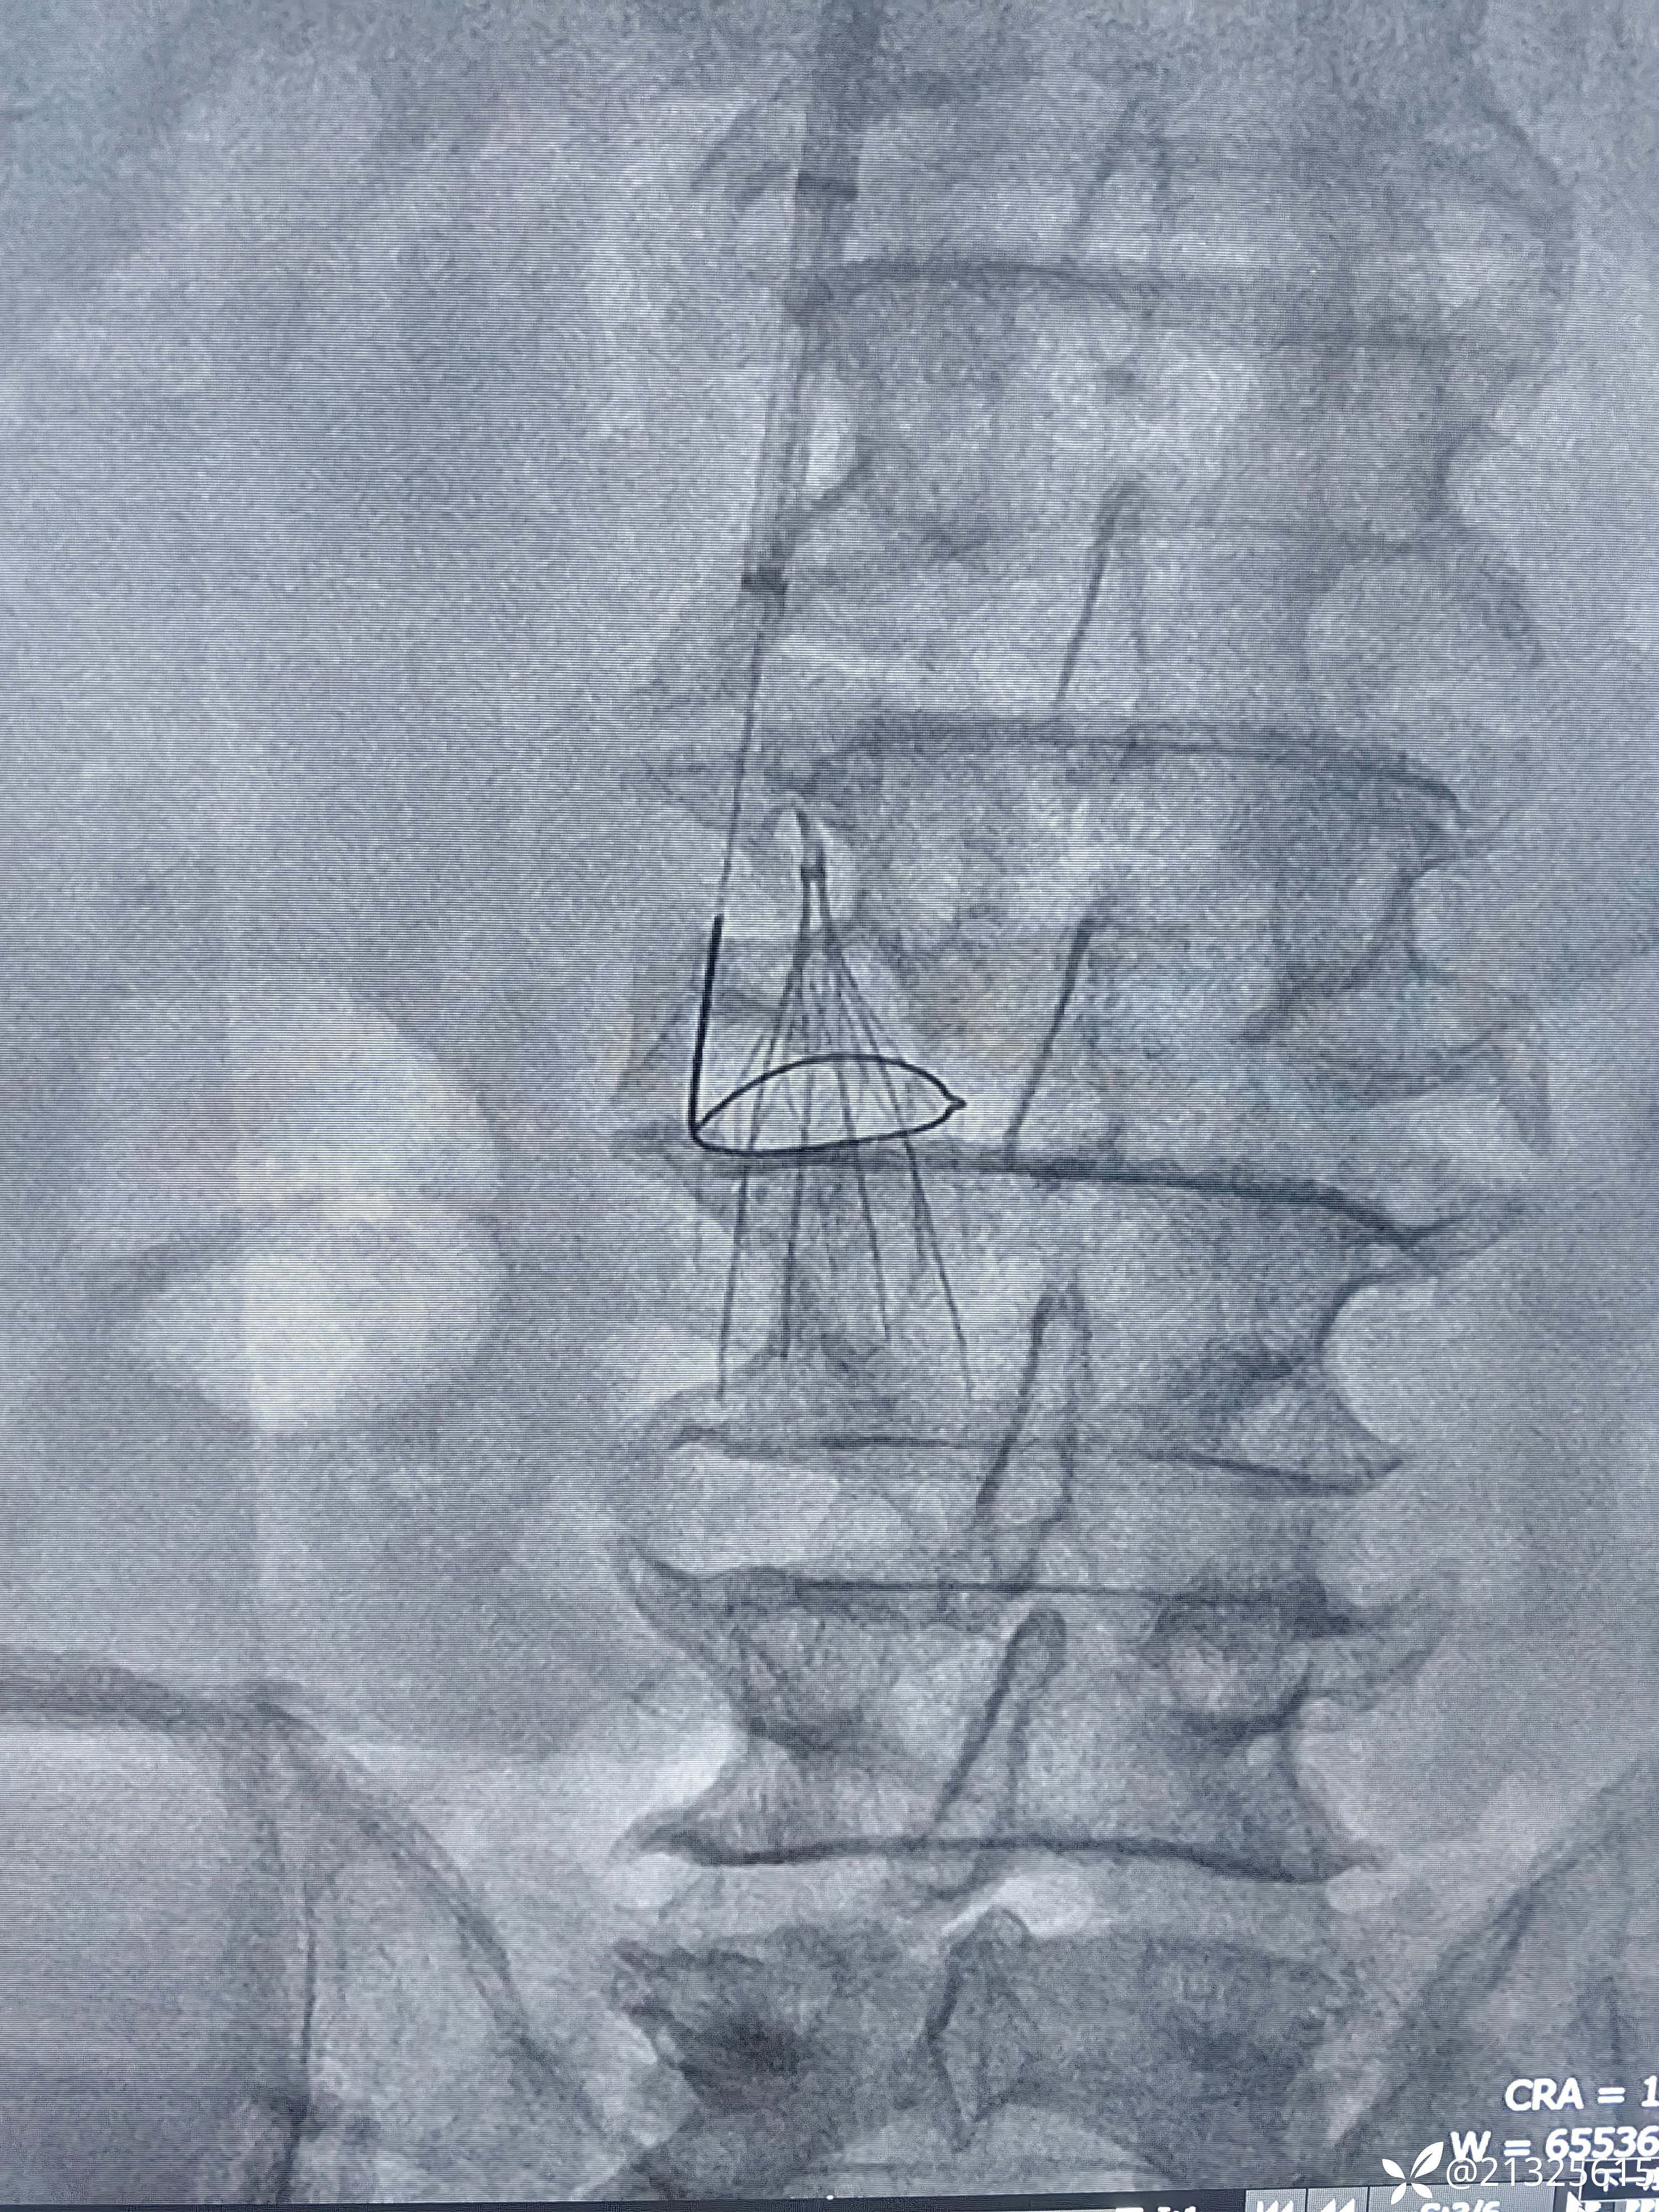

送入取滤器套件,以环状抓捕器套住滤器顶端小钩,

推入外壳将其纳入鞘管取出